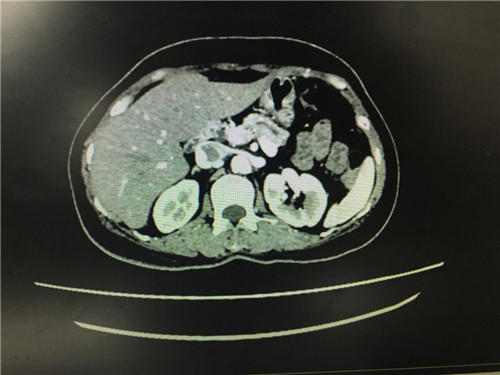

2月12日,普外科收治了一名女性患者,该患者入院一个月前,无明显诱因出现上腹部疼痛不适,呈间断性,向腰背部放射,有恶心,无呕吐,近一个月体重下降了5kg。门诊查上腹部CT提示:胰颈部新生物并胰管扩张;副脾。

患者病情复杂,在潘承恩教授和全科医生的讨论下,结合检验及检查结果,术前胰腺颈体部肿瘤诊断明确,科室积极制定手术方案,详细向家属探明病情并取得合作。2月21日,由普外科史和平主任、梁鹏锋医师主刀,在王谦、李垚磊医师配合下,成功对该患者实施了剖腹探查、全胰腺切除、脾脏切除术。手术中发现,患者胰腺颈体部可触及一大小约4cm包块,胰头部质软,胰腺体尾部质硬,遂决定行胰腺颈体尾部切除及脾脏切除术。在胰腺近侧断端切取部分胰腺组织送术中快速冰冻,提示查见异型增生的胰腺腺泡样组织,联系病理科考虑癌细胞残留,术中向家属谈明病情并取得同意,遂行胰十二指肠切除术,手术顺利,术后生命体征平稳,并于术后第四日进行了复查CT结果良好。